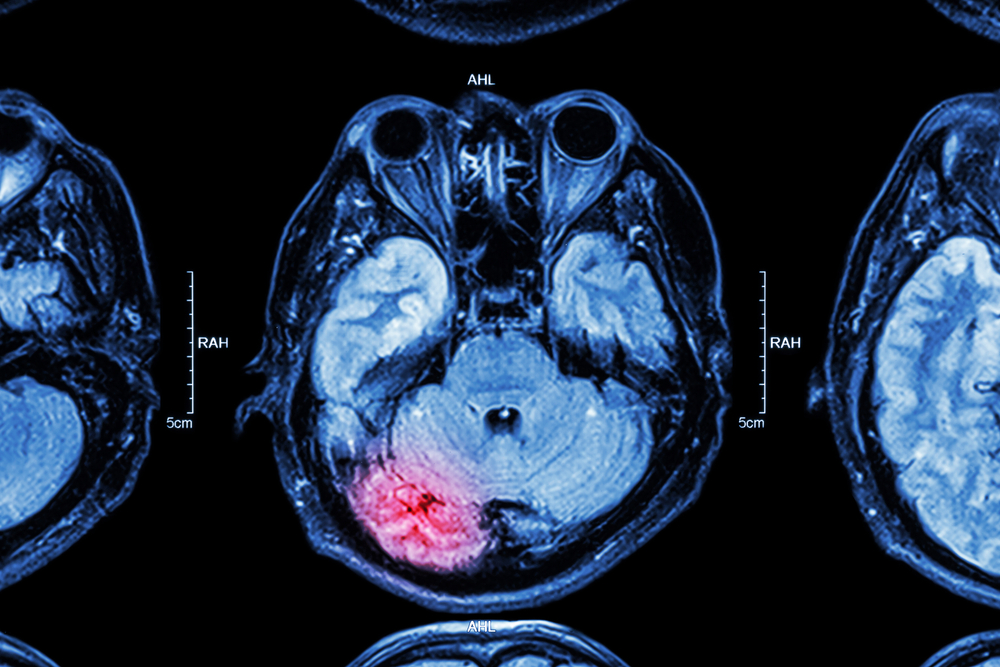

A traumatic brain injury, or TBI, is any injury caused by direct or indirect trauma to the brain. Because the brain is responsible for controlling the entire body, a TBI can lead to significant complications in nearly any body part. Below, we explore five surprising facts you may not know about TBIs.

No two individuals are alike, and no two TBIs are either. Because every TBI case is different, treatment options can vary significantly based on factors such as the location of the injury, the extent of the damage, and the duration of unconsciousness. Depending on the circumstances, TBI treatment may involve: